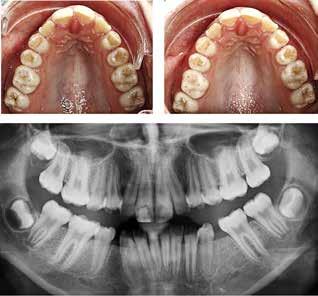

BAGGRUND – Denne kasuistik beskriver en patient, hvor der blev valgt protetisk behandling i ung alder.

PATIENTTILFÆLDE – En niårig pige havde stort behandlingsbehov og smerter fra tænderne på grund af tandudviklingsforstyrrelse. Der var flere gange forsøgt restaurering med komposit, som ikke fungerede. Laminater i feldspatkeram blev valgt for at fjerne mindst mulig tandsubstans, øge holdbarheden på restaureringerne og forbedre æstetikken. Patientens motivation, meninger og kooperationsevne var vigtige for behandlingsvalget, da behandlingen var tidkrævende og til tider udmattende for en ung patient.

KONKLUSION – Resultatet var vellykket og medførte forbedret livskvalitet. Protetisk behandling med adhæsiv teknik kan være et godt behandlingsalternativ for børn og unge på ret indikation.

EMNEORD Adhesives | amelogenesis imperfecta | ceramics | pediatric dentistry | quality of life

Protetisk behandling med adhæsiv teknik –et alternativ i ung alder?

Accepteret til publikation den 26. marts 2024 Tandlægebladet 2024;128:758-62

VED BEHOV FOR OMFATTENDE TANDRESTAURERING HOS BØRN OG UNGE kan flere behandlingsalternativer være aktuelle (1). Restaurering med fyldningsmaterialer er som regel førstevalg, men i nogle tilfælde fungerer dette ikke godt nok. Ved udarbejdelse af behandlingsplan må klinikerne kende til mulige behandlingsalternativer og vurdere disse på baggrund af kliniske fund, patientens symptomer og kooperationsevne samt patientens ønsker og planlægge behandling i et livsløbsperspektiv.

PATIENTTILFÆLDE

Beskrivelse af patienten Patienten blev henvist til specialistuddannelsen i pædodonti ved Universitetet i Oslo, da hun var syv år gammel, for diagnostik og behandling af tandudviklingsforstyrrelse i primære og permanente tandsæt. Pigen havde pollenallergi, var ellers sund og rask og havde intet medicinforbrug.

Klinisk undersøgelse viste emaljehypoplasier og hypomineralisering på 1+, +1, 2-, 1-, -1 og -2 (Fig.1). Hun havde Angle klasse II, pladsmangel i begge kæber og agenesi af -5. Der var isninger ved spisning og tandbørstning. Fundene var forenelige